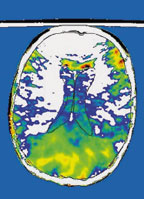

Уже в ближайшем будущем новые технологии начнут помогать нам контролировать свой разумВаш мозг — всего лишь еще одна разновидность вычислительного устройства. Убедитесь в том, что загрузили последние обновления и установили новейшую версию операционной системы. Такую судьбу человечеству рисует Дэвид Песковитц, редактор блога BoingBoing.net и научный директор Института будущего.

Пытаясь ‘настроить’ свой мозг на нужный лад, мы потребляем кофе и другие стимуляторы. Но по сравнению с технологией будущего, в которой найдут отражение все самые передовые достижения нейробиологии, это грубые и неэффективные «инструменты».

«Уже в ближайшем будущем новые технологии начнут помогать нам контролировать свой разум, — заметил Песковитц, которому на недавней конференции O’Reilly ETech в Сан-Диего, посвященной перспективным технологиям, досталась роль модератора дискуссии, посвященной ‘будущему настройки разума’. — У нас появится возможность менять свой менталитет по собственному усмотрению».